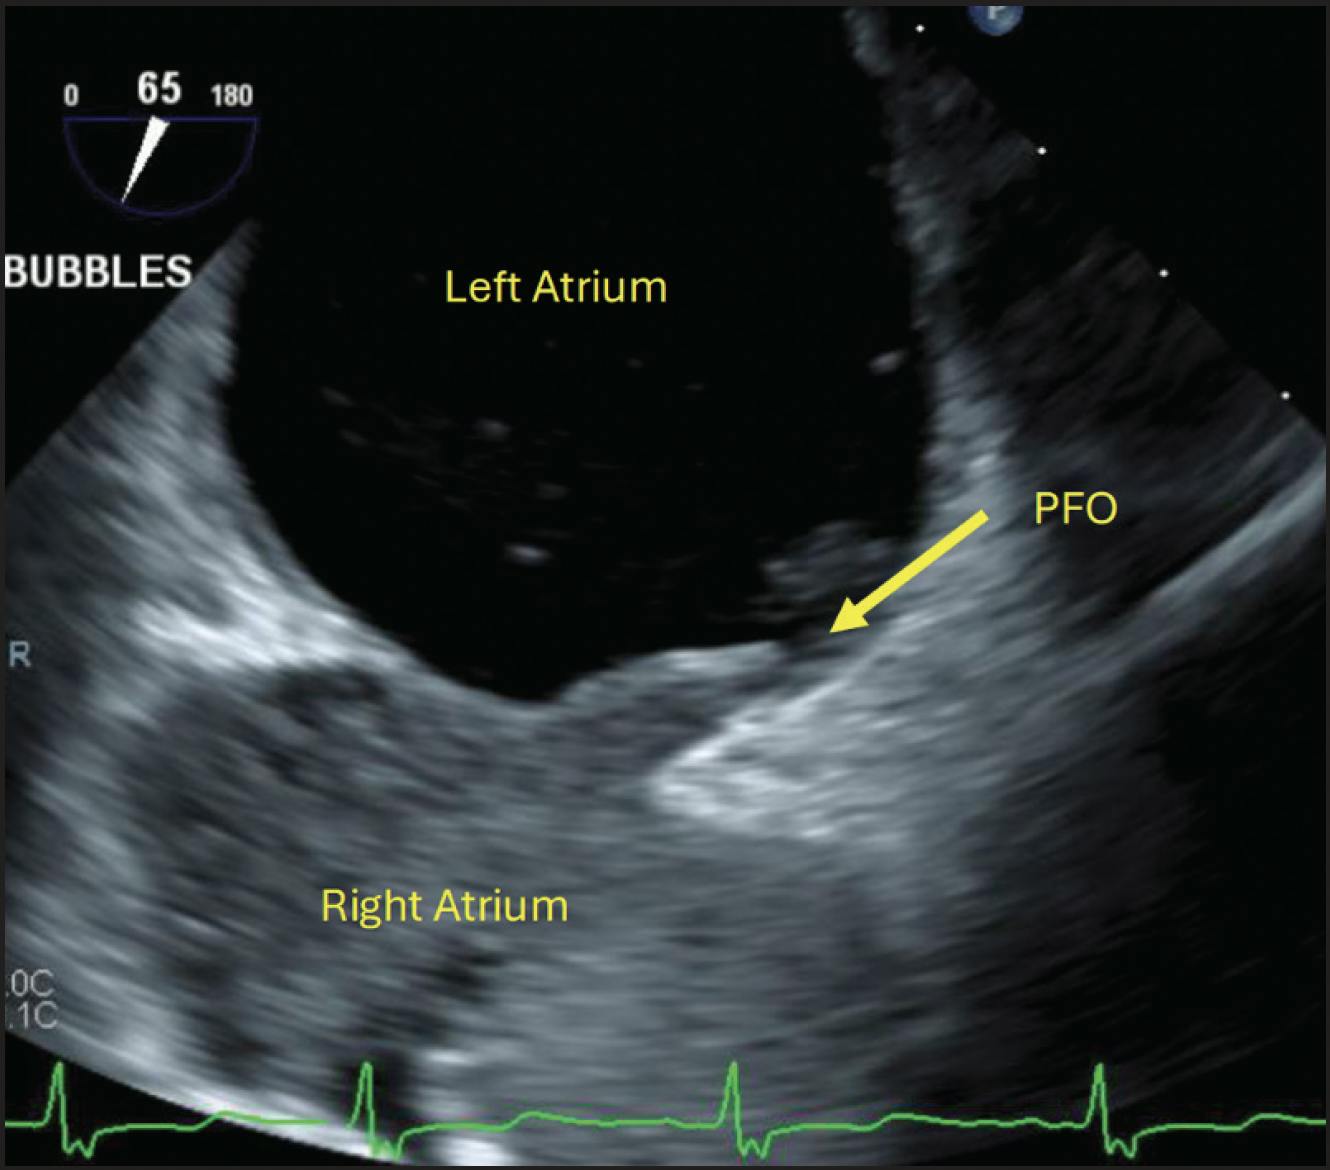

Prior to discharge, a transesophageal echocardiography (TEE) confirmed the presence of a patent foramen ovale (PFO) with an atrial septal aneurysm measuring > 10 mm (Figure 5). Head CT showed no signs of acute stroke. The patient was discharged to rehabilitation with follow-up arranged in a post-PE clinic and with cardiology for consideration of PFO closure.

Figure 5. TEE confirming the presence of a PFO.